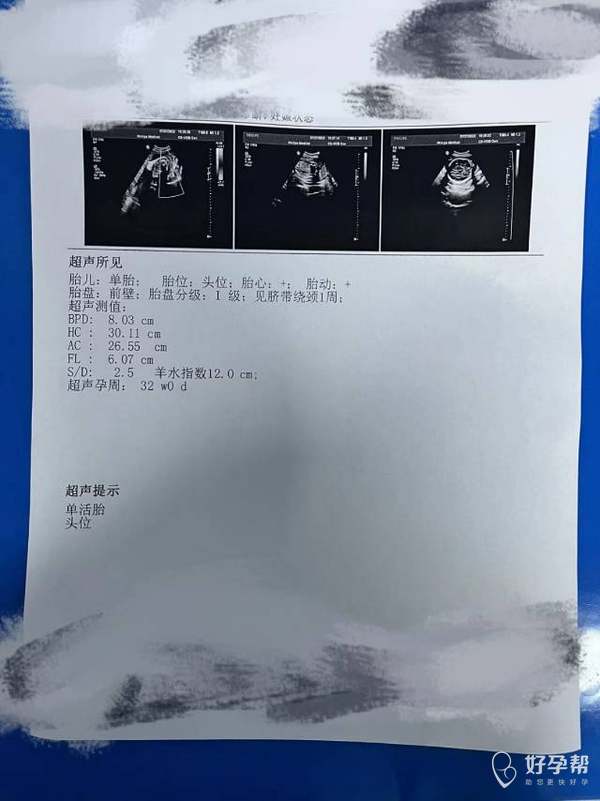

大夫这个腿可以吧没事吧不短吧担心死了

这个彩超看孩子腿不短,放心吧。祝好孕。